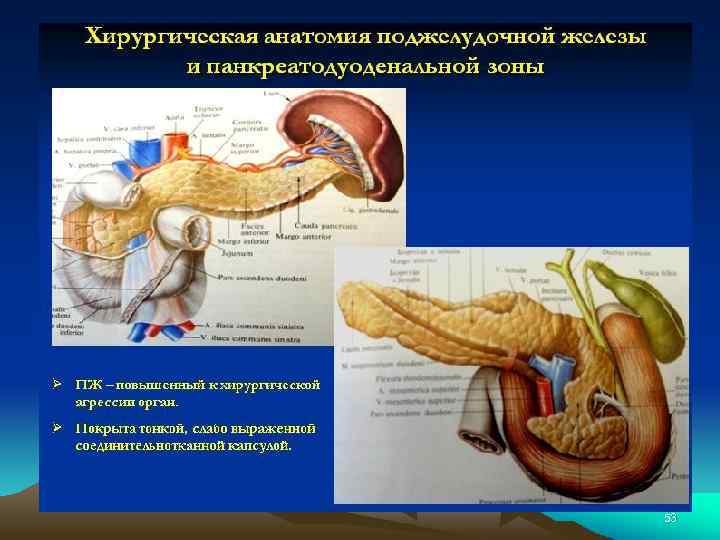

• Поджелудочная железа и двенадцатиперстная кишка 1 — селезенка; 2 — брюшная аорта; 3 — нижняя полая вена; 4 — воротная вена; 5 — верхний край поджелудочной железы; 6 — верхняя часть двенадцатиперстной кишки; 7 — хвост поджелудочной железы; 8 — тело поджелудочной железы; 9 — верхний изгиб двенадцатиперстной кишки; 10 — передний край поджелудочной железы; 11 — нижний край поджелудочной железы; 12 — тощая кишка; 13 — головка поджелудочной железы; 14 — нисходящая часть двенадцатиперстной кишки; 15 — восходящая часть двенадцатиперстной кишки; 16 — горизонтальная часть двенадцатиперстной кишки; 17 — нижний изгиб двенадцатиперстной кишки 6